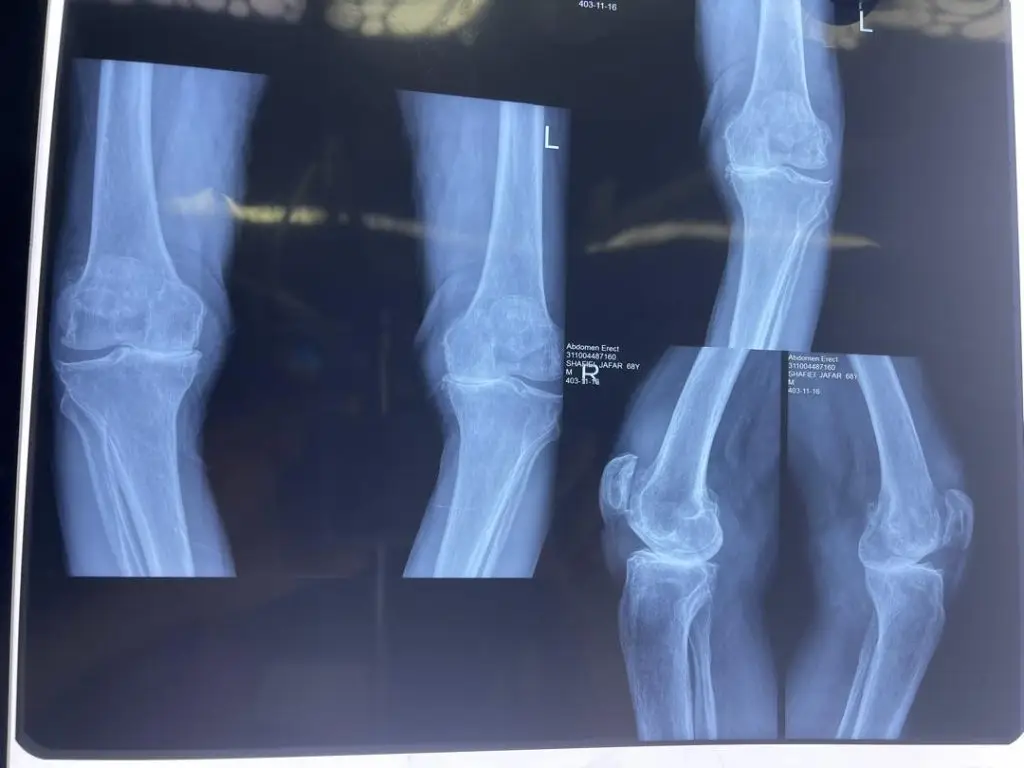

این عمل معمولاً برای افرادی توصیه میشود که به آرتروز پیشرفته، تغییر شکل زانو (مثل زانو پرانتزی یا ضربدری) یا تخریب مفصل ناشی از روماتیسم یا آسیبهای شدید دچار شدهاند.

- آرتروز پیشرفته زانو (Osteoarthritis):

زمانی که غضروف مفصل کاملاً از بین رفته و استخوانها روی هم ساییده میشوند، درد مزمن و محدودیت حرکتی شدید بروز میکند. - روماتوئید آرتریت و سایر آرتریتهای التهابی:

در مواردی که التهاب شدید باعث تخریب زودرس مفصل شده و درمان دارویی بیاثر باشد، تعویض مفصل راهحل اصلی است. - آسیبهای شدید یا دفورمیتی زانو:

شکستگیهای گسترده یا انحرافات زانو (پرانتزی و ضربدری) ممکن است به تخریب مفصل منجر شوند که با جراحی اصلاح میشود. - ناتوانی در انجام فعالیتهای روزمره: